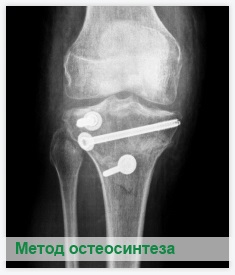

Неправильное лечение несросшихся переломов приводит к образованию псевдоартрозов (ложных суставов), которые требуют оперативного лечения. Такое лечение обычно состоит в резекции концов костных отломков и последующем остеосинтезе. Если отломки не могут быть соединены до полного соприкосновения, применяется пересадка кости.

При выборе метода операции учитываются индивидуальные особенности пациента и клинико-анатомические изменения в области ложного сустава, прошедшие с момента перелома сроки, локализация и характер перелома.